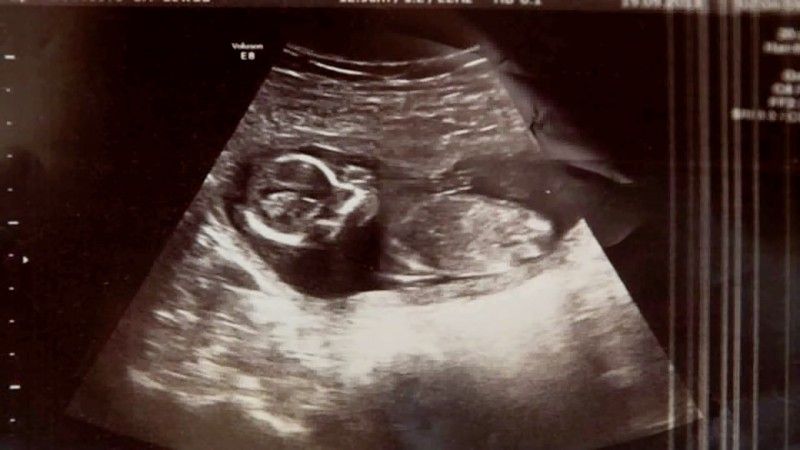

Οι γιατροί στο νοσοκομείο ελέγχουν με υπέρηχο την κοιλιά της Μισέλ για μια τελευταία φορά πριν προχωρήσουν σε απόξεση της μήτρας και βρίσκουν το αλάνθαστο χτύπο της καρδιάς ενός εμβρύου! Η Μισέλ είναι έγκυος, παρά την αποβολή και τα χάπια της εκτρώσης. Αποδεικνύεται ότι ήταν αρχικά έγκυος με δίδυμα, αλλά μόνο το ένα μωράκι απέβαλλε ο οργανισμός Πώς το δεύτερο μωρό κατάφερε να επιβιώσει, ακόμα και οι γιατροί δεν μπορούν να εξηγήσουν!

“Ο γιατρός βγήκε και επέστρεψε πάλι με ένα μεγαλύτερο σε ηλικία συνάδελφο, ο οποίος επανέλαβε τη διαδικασία και, στη συνέχεια, είπε, “Δεν θα μας πιστέψετε, αλλά έχουμε έναν χτύπο καρδιάς.” Αυτό ήταν το καλύτερο συναίσθημα που είχα ποτέ , λέει η Μισέλ. Στο τέλος, το μωρό γεννήθηκε υγιέστατο και άφησε άναυδους τους γιατρούς και τους γονείς.